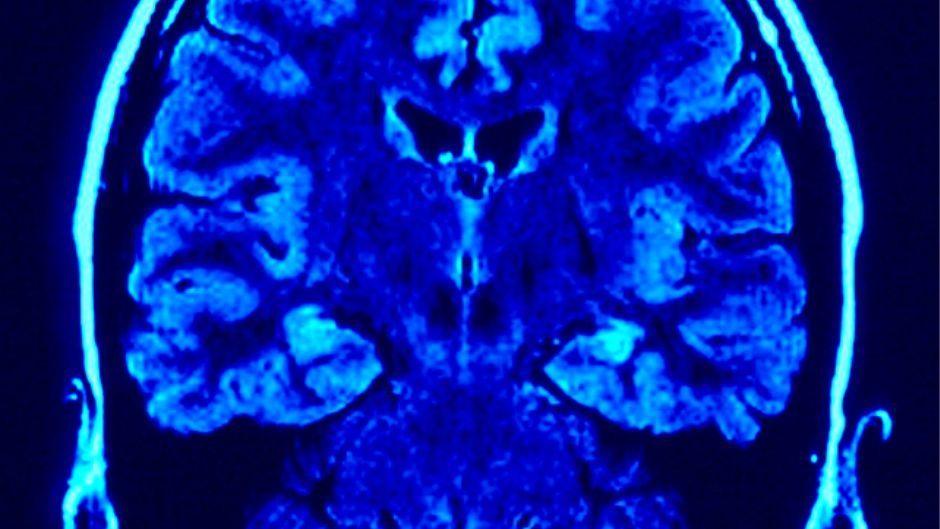

Moždani udar uzrokuje poremećaj u moždanoj cirkulaciji zbog čega su određeni dijelovi mozga nedovoljno opskrbljeni kisikom i hranjivim tvarima, a to vodi do oštećenja i odumiranja živčanih stanica. Uzroci su ugrušak koji začepi arteriju i tako onemogući protok krvi ili pak puknuće krvne žile kada krv počinje prodirati u okolno tkivo. "Najčešći uzrok oštećenja krvnih žila u mozgu koja dovode do moždanog udara je ateroskleroza — bolest koja dovodi do stvaranja naslaga masnoća, vezivnog tkiva, ugrušaka, kalcija i drugih tvari u stijenci krvne žile, što uzrokuje sužavanje, začepljenje i/ili slabljenje stijenke krvne žile", objašnjavaju na internetskoj stranici Hrvatskog društva za prevenciju moždanog udara (HDPMU).